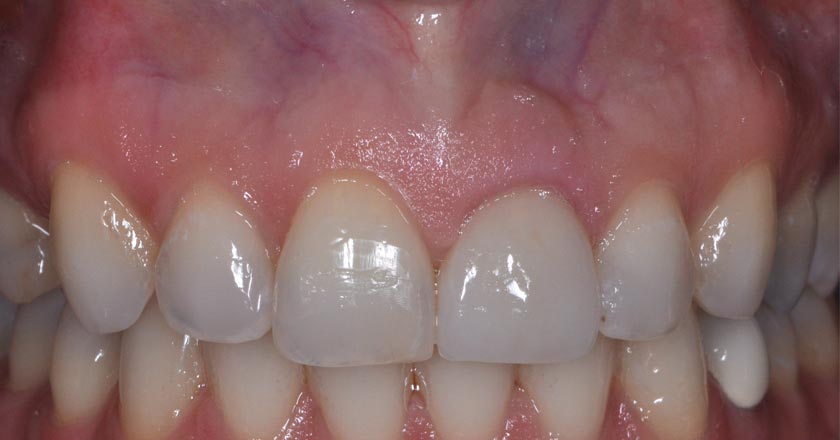

Implant - Before And After